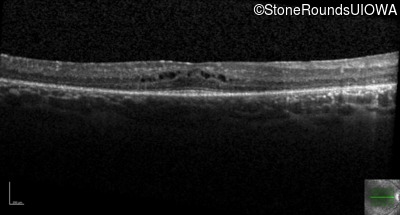

Optical Coherence Tomography - Right - 20/40 -1 sc

Exemplar / OCT Stack

OCT Stack

Optical Coherence Tomography - Left - 20/32 sc